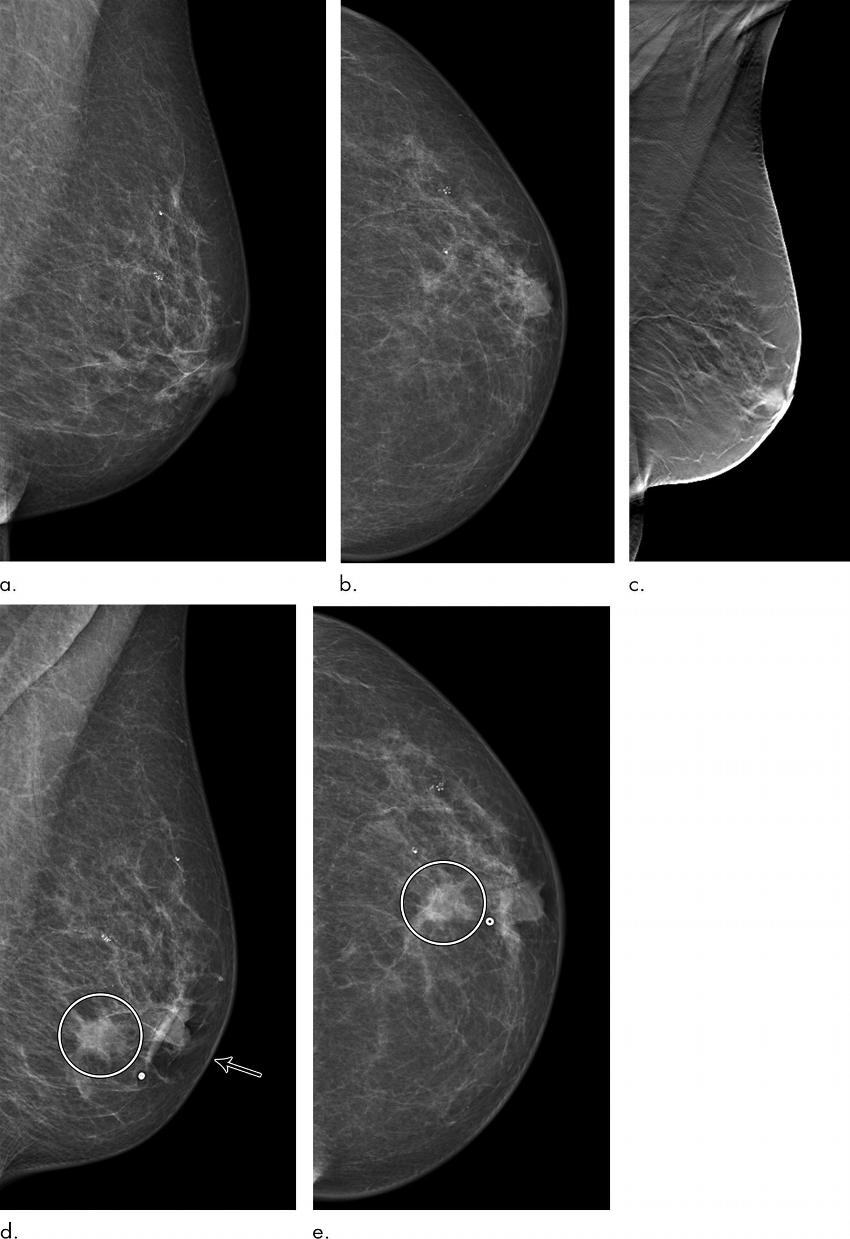

Figure 2. Images in a 72-year-old woman who was diagnosed with a 13-mm lymph node-negative invasive lobular carcinoma luminal B–like human epidermal growth factor receptor 2 breast cancer 18 months after a screening negative for cancer in the Malmö Breast Tomosynthesis Screening Trial. (a) Mediolateral oblique and (b) craniocaudal digital mammography (DM) images at screening. The slight retraction of the nipple was unchanged compared with previous DM screening images. (c) Digital breast tomosynthesis at screening. DM images of (d) mediolateral oblique and (e) craniocaudal views at diagnosis, small marker at lump location. Increased nipple retraction (arrow) and central mass (circle on d and e).